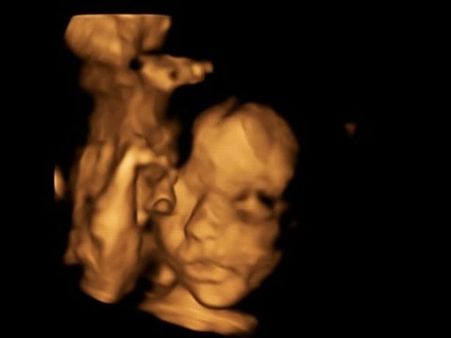

The 26-year-old woman and her partner were given the option to terminate the pregnancy after the tests revealed that the unborn baby had spina bifida. The medics discovered this in a routine 20-week scan where they realised that the unborn baby's head was not the right measurement.

The doctors offered the couple a new option called as foetal surgery where they would fix the unborn child's condition even before she is born. The surgery involved removing the unborn baby from the mother's womb and repairing the spinal cord of the child, so that the baby has greater chances of leading a normal life.